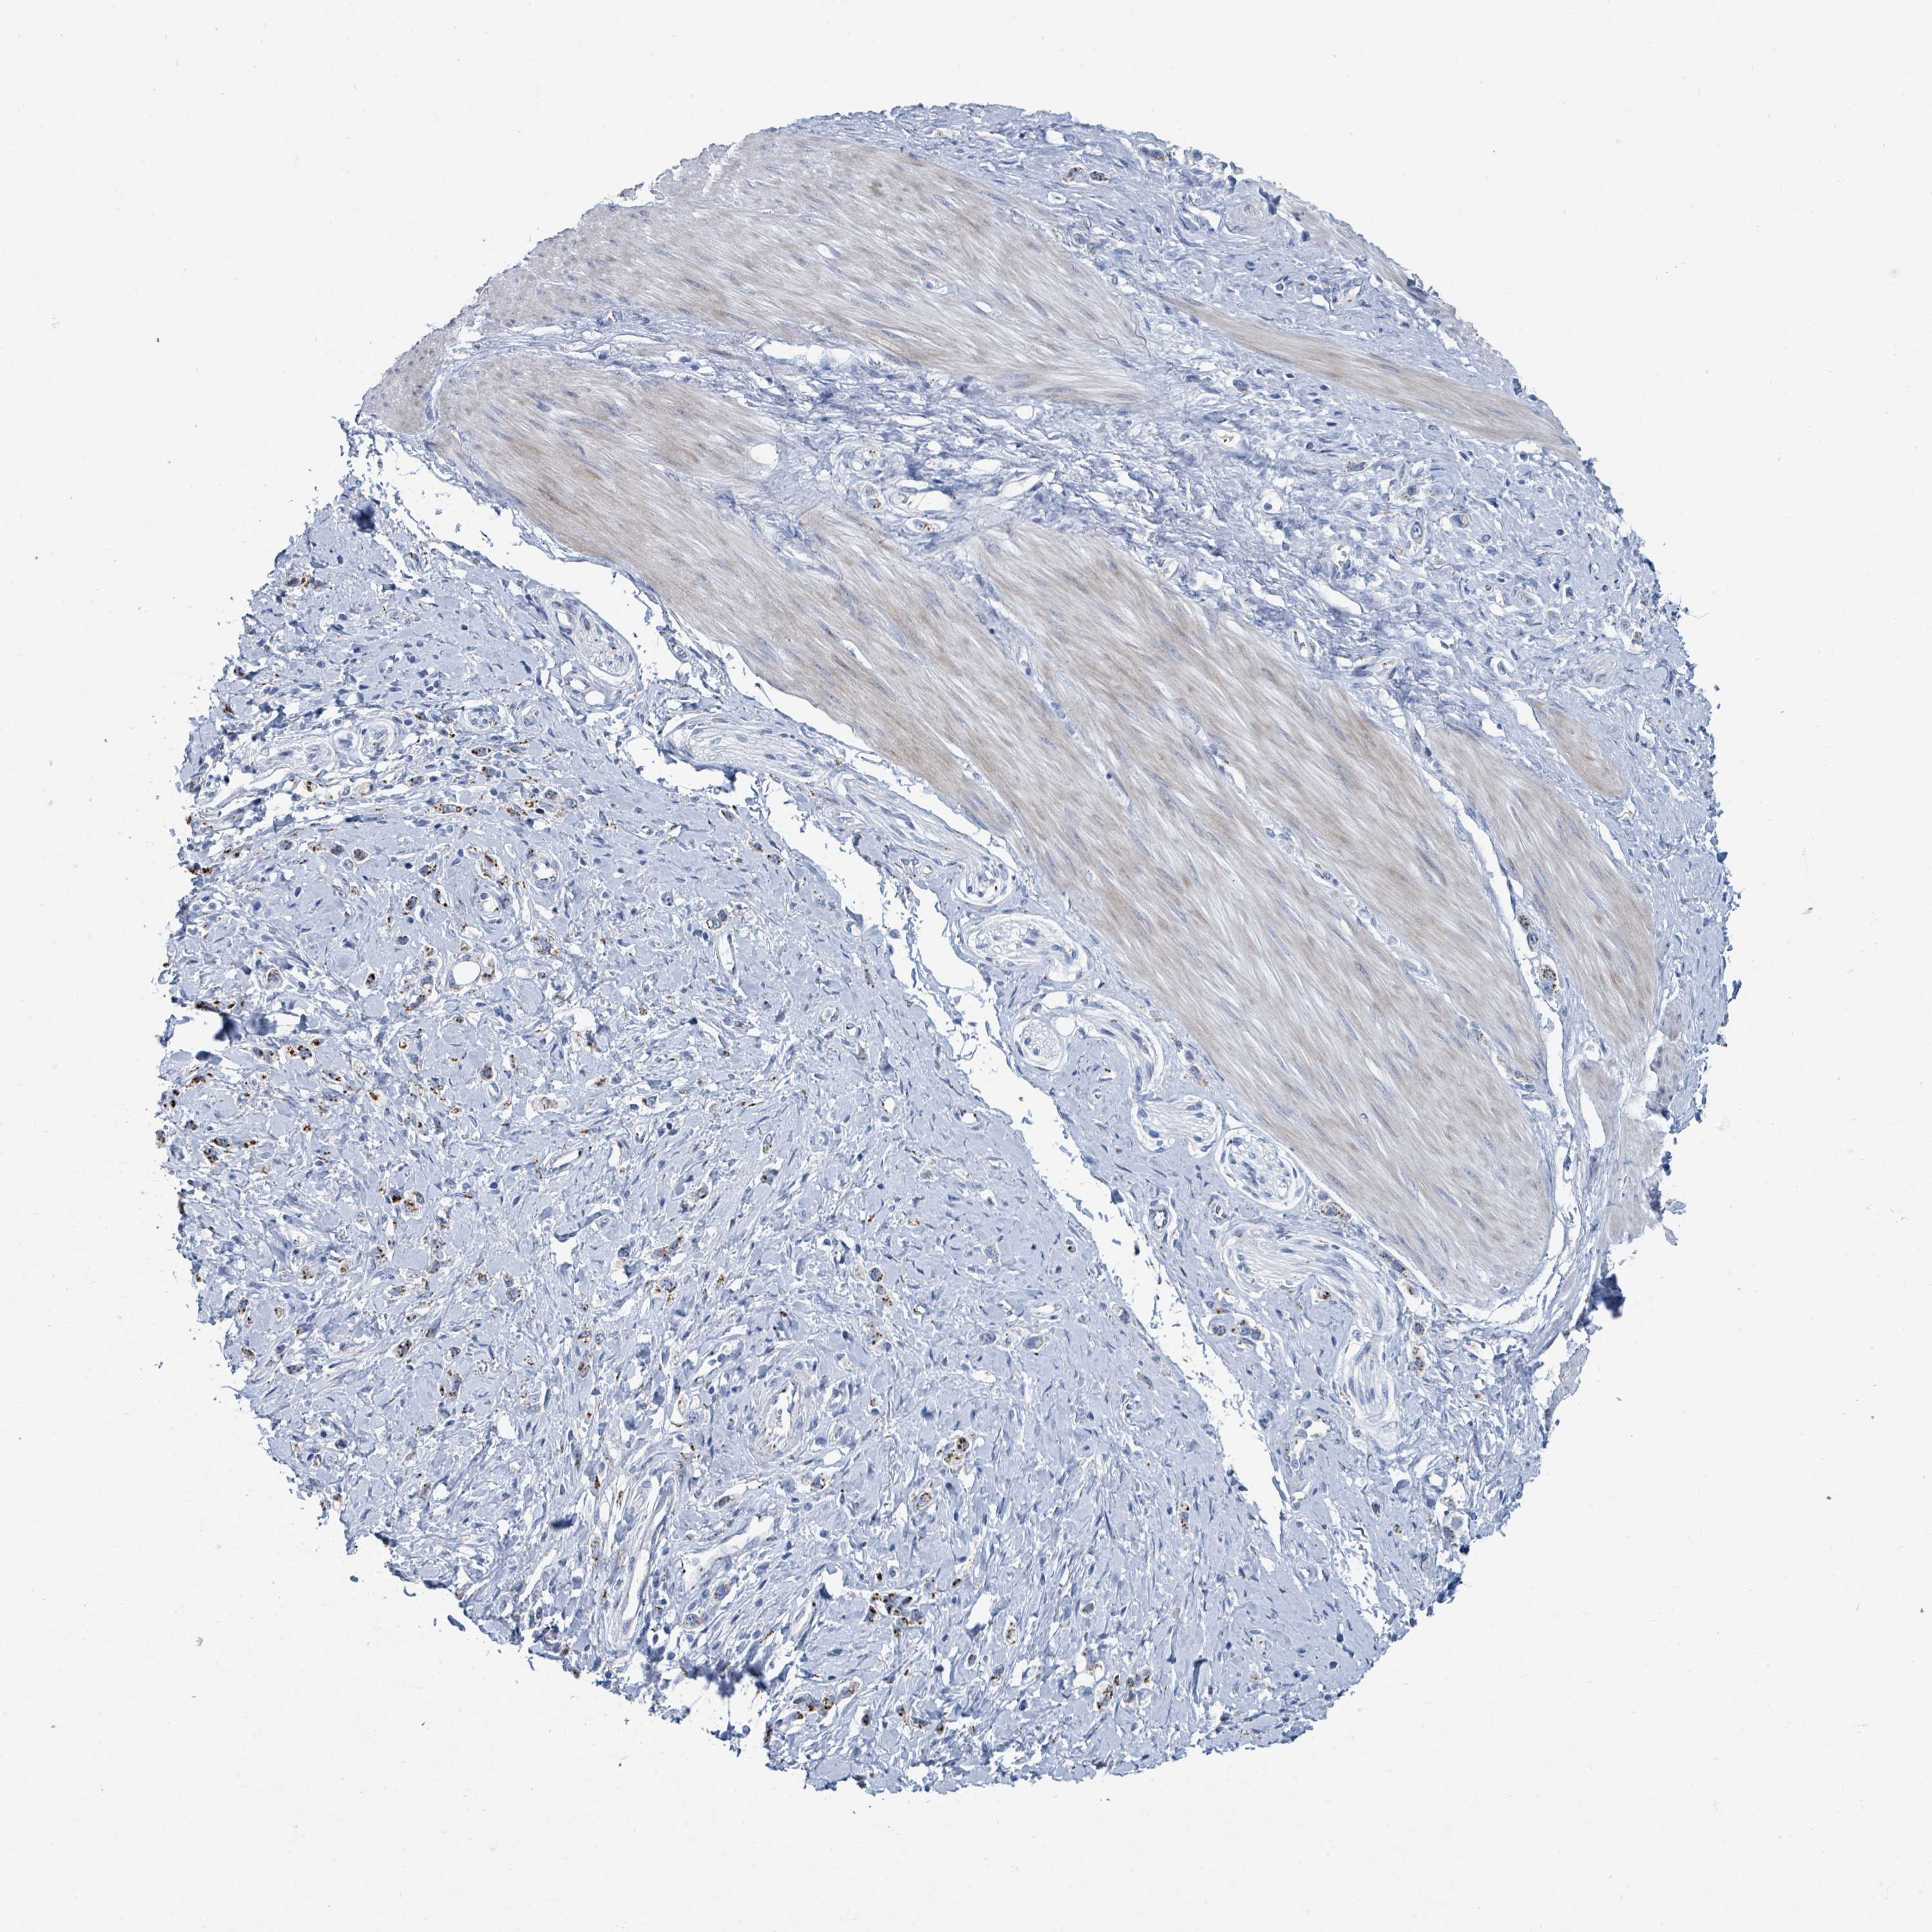

STOMACH CANCER - Protein expressioni

A mouse-over function shows sample information and annotation data. Click on an image to view it in a full screen mode. Samples can be filtered based on level of antibody staining by selecting one or several of the following categories: high, medium, low and not detected. The assay and annotation is described here.

Note that samples used for immunohistochemistry by the Human Protein Atlas do not correspond to samples in the TCGA dataset.

Antibody stainingi

Antibody staining in the annotated cell types in the current human tissue is reported as not detected, low, medium, or high, based on conventional immunohistochemistry profiling in selected tissues. This score is based on the combination of the staining intensity and fraction of stained cells.

Each image is clickable and will lead to virtual microscopy that enables deeper exploration of all samples and also displays staining intensity scores, fraction scores and subcellular localization as well as patient and tissue information for each sample.

Antibody HPA041575

Antibody HPA048098

Adenocarcinoma, NOS